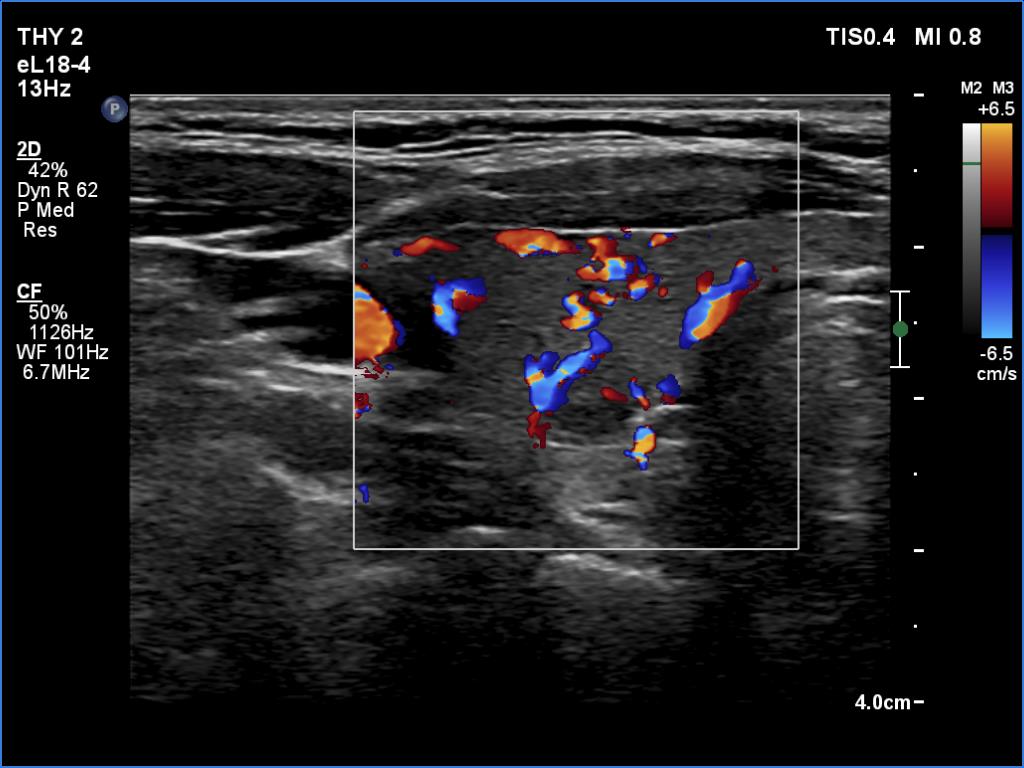

Right lobe, color Doppler mode

Left lobe, color Doppler mode